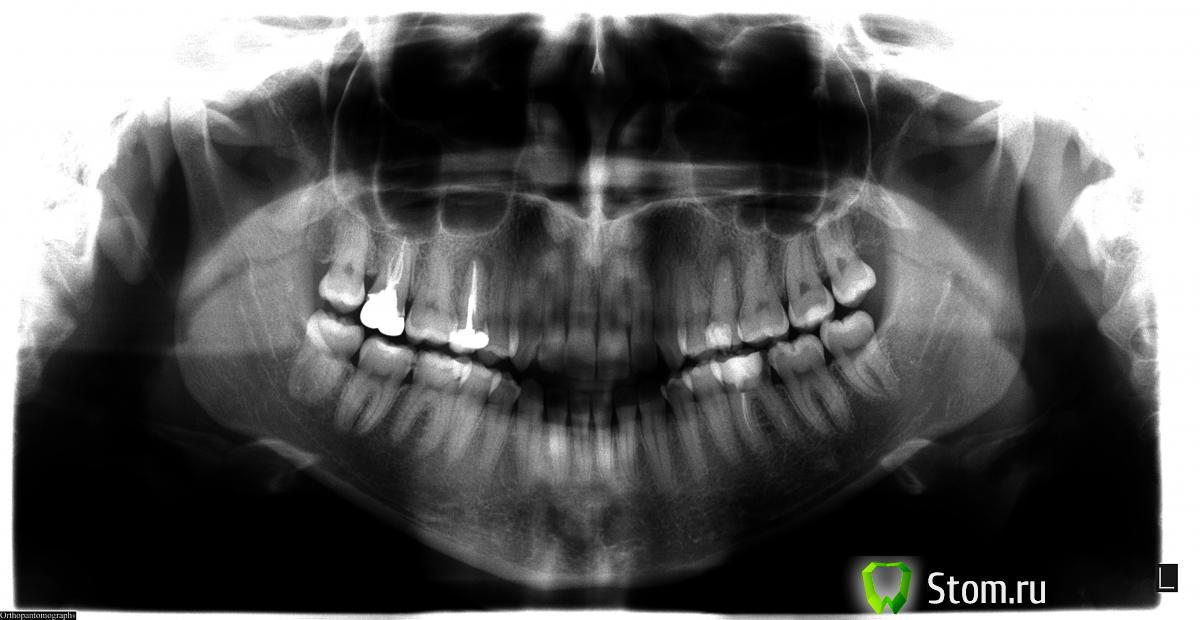

Ульяна1 Опубликовано 6 января, 2012 Поделиться Опубликовано 6 января, 2012 Добрый день!у меня 2 кисты на верхних 5-ках.была у 3ех стоматологов ,все говорят разное.посоветуйте какой план лечения выбрать???у меня бывает аллергический насморк.сделала пантограмму 1ый врач сказал что левую пятерку нужно перепломбировать и запустить пасту немного выше в кисту(разве не лекарство пускают в кисту???),и она начнет рассасываться.про правую пятерку сказала,что нужно сделать резекцию у хирурга!2ой врач сдедала снимки каждого зуба и сказала:левая киста большая и она расположена очень близко с соседним корнем,зуб мертвый и лучше его удалить,так как резекция удалит пол зубика и ему не на чем будет держаться и смысла в ней нет,так как зуб никакойа насчет левой кисты- можно попробывать полечить,но только 50% того,что лечение поможет.потом нужно будет надеть коронку,а это большая нагрузка на зуб.3ий врач сказал левый лечим,в несколько посещений,потом ставим вкладку.правый-резекция.потом пустое место заполняется костной крошкой.не знаю что делать.... Ссылка на комментарий

Ульяна1 Опубликовано 6 января, 2012 Автор Поделиться Опубликовано 6 января, 2012 я вас поняла,а если целесообразности в лечении нет,то тогда удаление зубов или резекция на ваш взгляд?скажите,когда я смотрю на снимок верхней 7-ки,вижу что как-будто пломбировочный материал находится оч высоко.это нормально? Ссылка на комментарий

kriokov Опубликовано 6 января, 2012 Поделиться Опубликовано 6 января, 2012 если зубы восстановить нельзя, они удаляются. В обл 7 изменений не увидел. Ссылка на комментарий